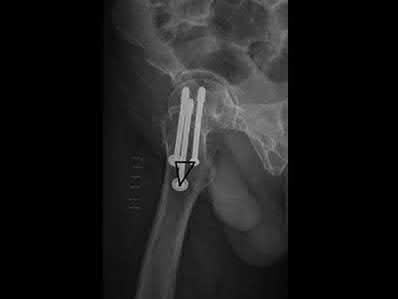

A 35-year-old-male sustains the fracture seen in Figure A. Which of the following reduction forces must be applied to the proximal fragment to correct the deformity commonly seen in these fractures?

Figure A demonstrates a displaced subtrochanteric femur fracture with an intact lesser trochanter. The pull of iliopsoas on the lesser trochanter as well as the intact external rotators and gluteal musculature results in the the proximal fragment being in a flexed and externally rotated or abducted position (the most common post operative deformity). Reduction manuevers must be biologically friendly but also counteract the flexion/abduction moment. Lundy's review article discusses evaluation and treatment of subtrochanteric fractures. The review article details the various implants often used which include 95 degrees plates, femoral reconstruction nails, or trochanteric femoral nails with interlocking options. Lundy's article discourages the use of the 135 degree screw and side plate combo due to high failure rates in these fracture patterns. Bedi et al also review treatment of these fractures and discuss common

problems of malunion, nonunion, and implant failure. The article reviews reduction techniques that are soft tissue friendly, as well as the use of appropriate implants in these fracture types.